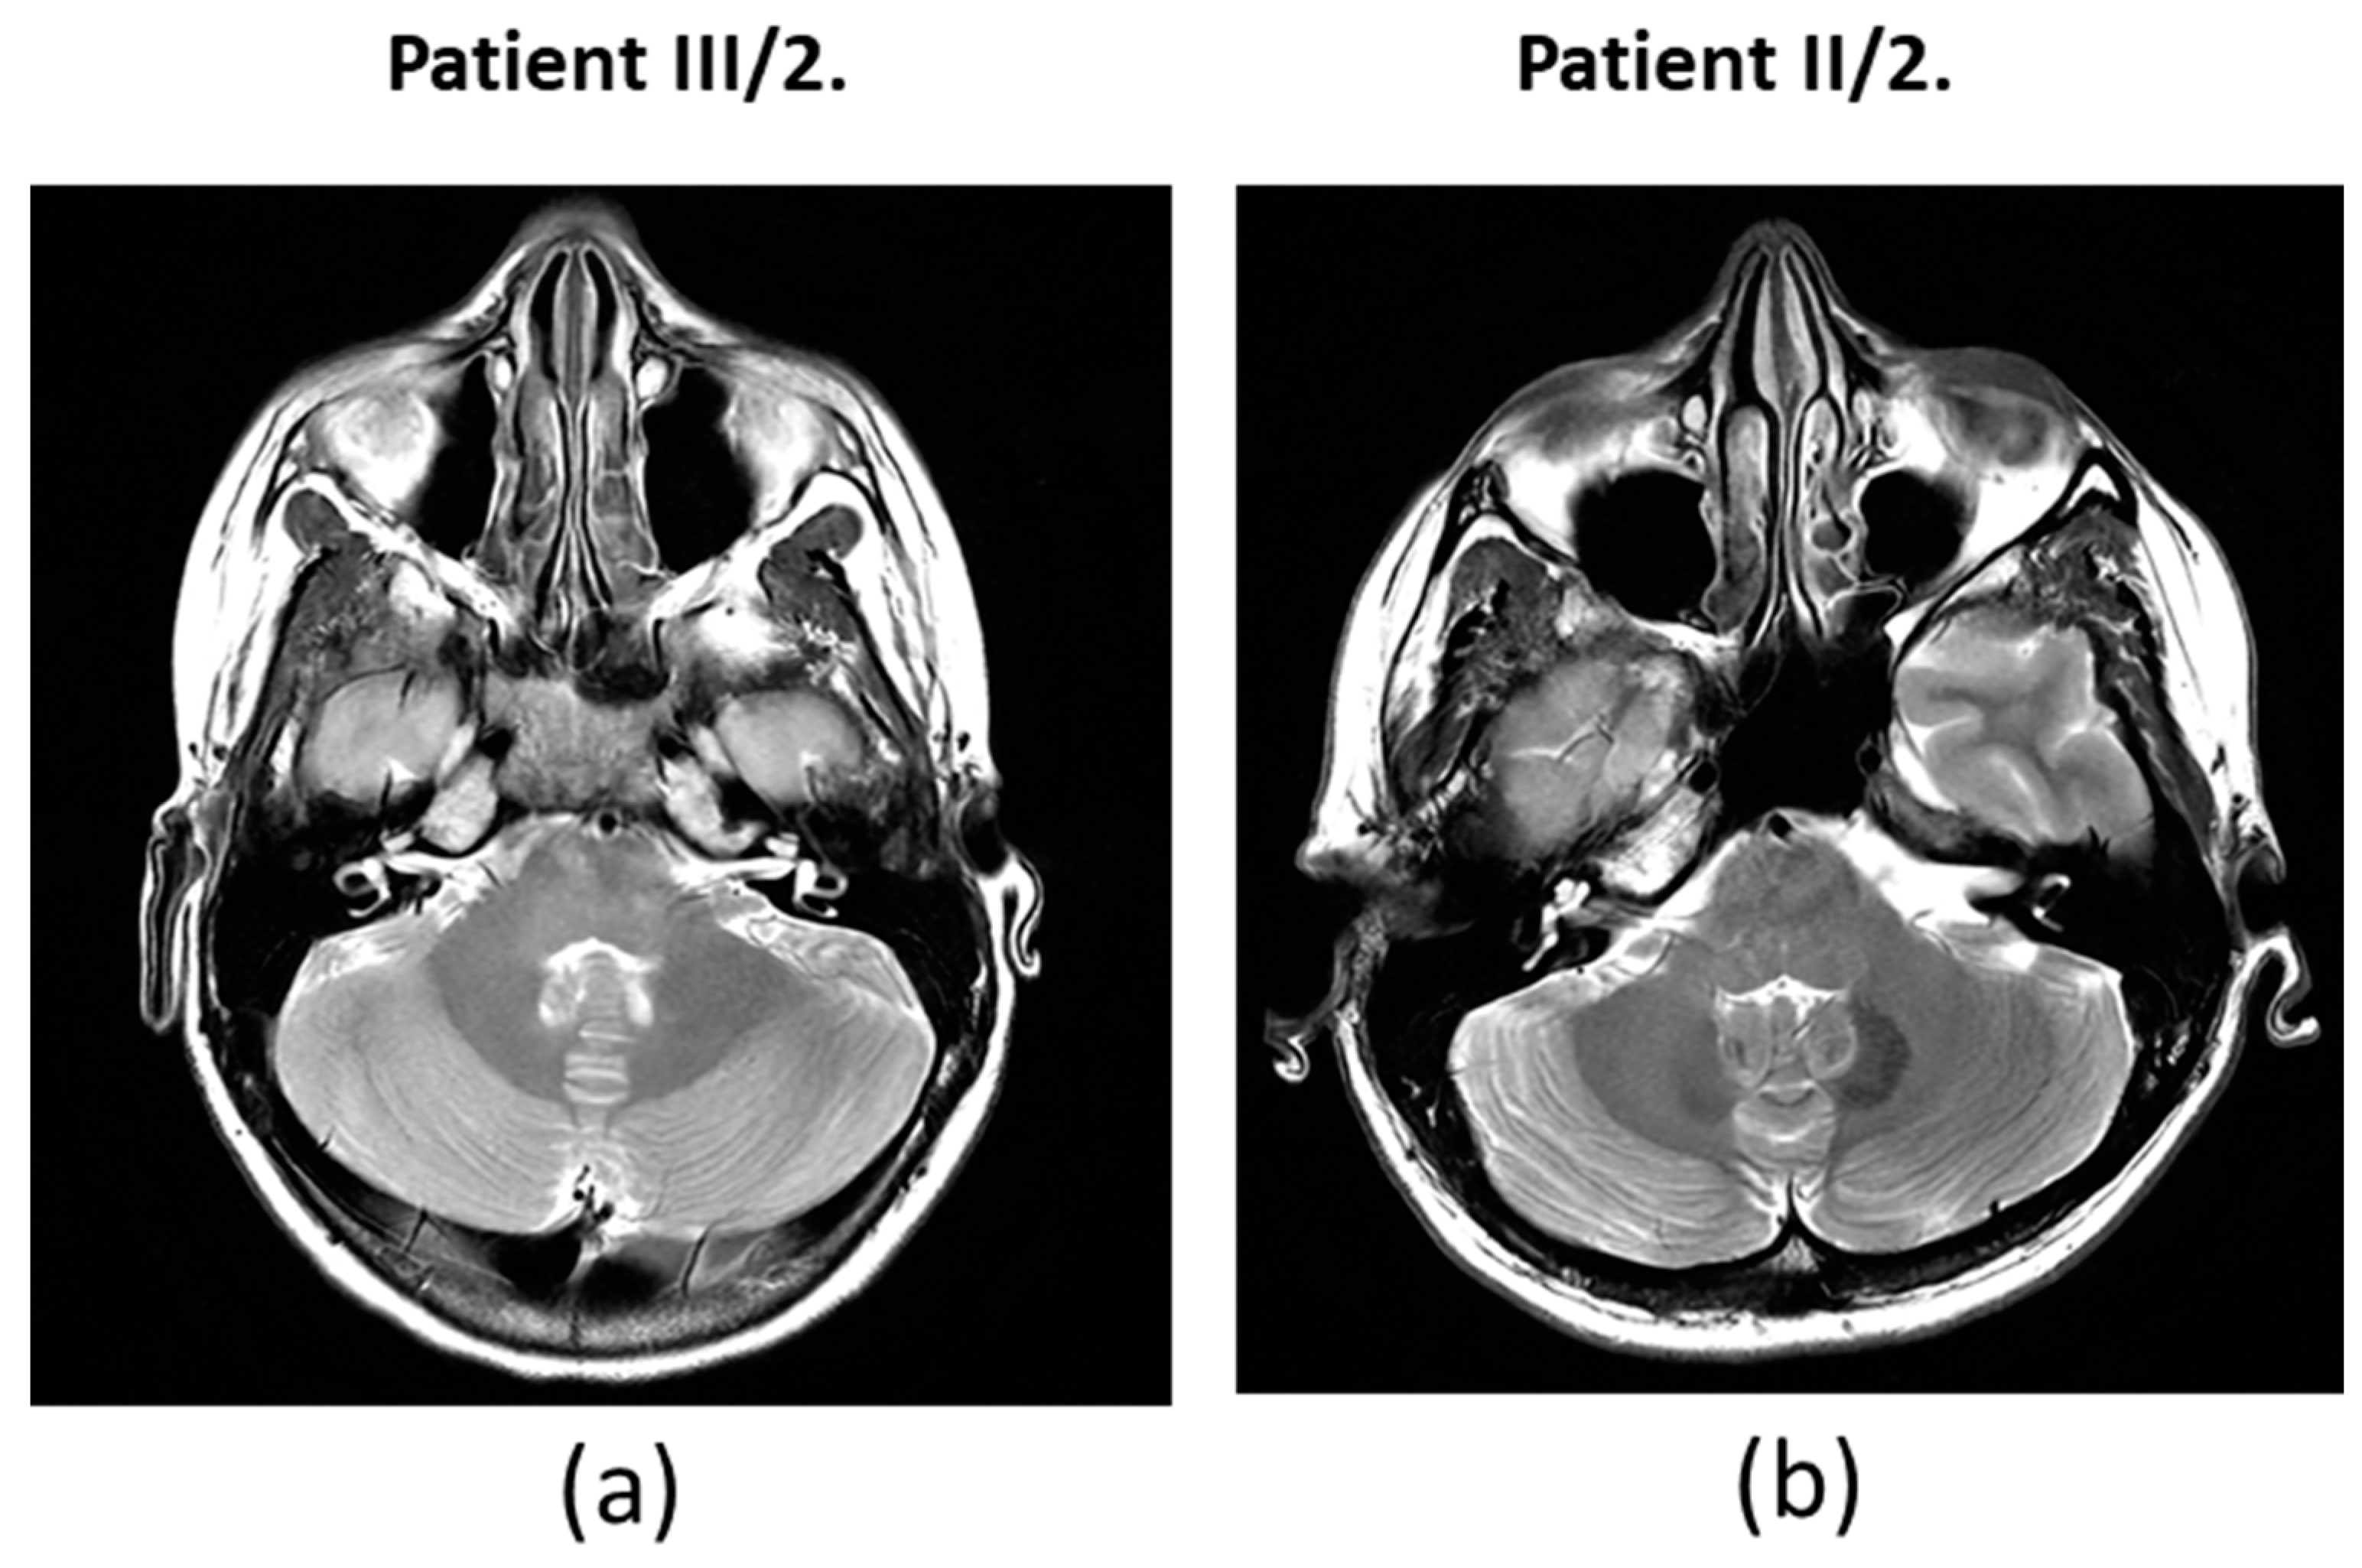

For the daughter (III/2), the PTA results showed a significantly impaired high-tone perception in the 2-8 kHz range (Figure 2), whereas the low-tone (0.125-1 kHz) range perception was normal. Tympanometry proved normal middle ear ventilation with 0 daPa and 0 daPa pressure (“A” type tympanogram). The ART was 500 and 2000 Hz, while absent at 4 kHz. At 70/60 dB SPL stimulus intensity the DP-grams showed nearly absent otoacoustic emissions in both ears (Figure 3). At 90 dB nHL stimulus intensity only the Vth waves were defined and reproducible on both sides. The objective hearing thresholds, measured at frequencies of 0.5, 1, 2 and 4 kHz were consistent with the PTA subjective results (right ear: 5, 30, 65 and 65 dB corHL; left ear: 30, 55, 75 and 80 dB corHL) (Figure 4). MRI did not reveal any abnormalities in the inner ears of the affected mother and daughter (Figure 5).

Due to the severe grade high frequency sensorineural hearing impairment in the 2-4 kHz range, a differential diagnosis between the cochlear vs. retrocochlear origin requires more complex diagnostic procedures, such as MRI. Although the MRI examination did not reveal any abnormalities of the inner ear and audiological findings partially support (on the contrary do not exclude) the cochlear origin of hearing loss, the cochlea may be the site of the lesion. This correlates well with the results on trrap knockdown and knockout zebrafish study: the observed reduced lateral line neuromasts, the decreased number of hair cells per neuromast and the abnormal stereocilia on the hair cells of the animals suggest relevant functional losses that resemble the diseased phenotype [5].

Figure 5. MRI of (a) patient III/2 and (b) patient II/2.